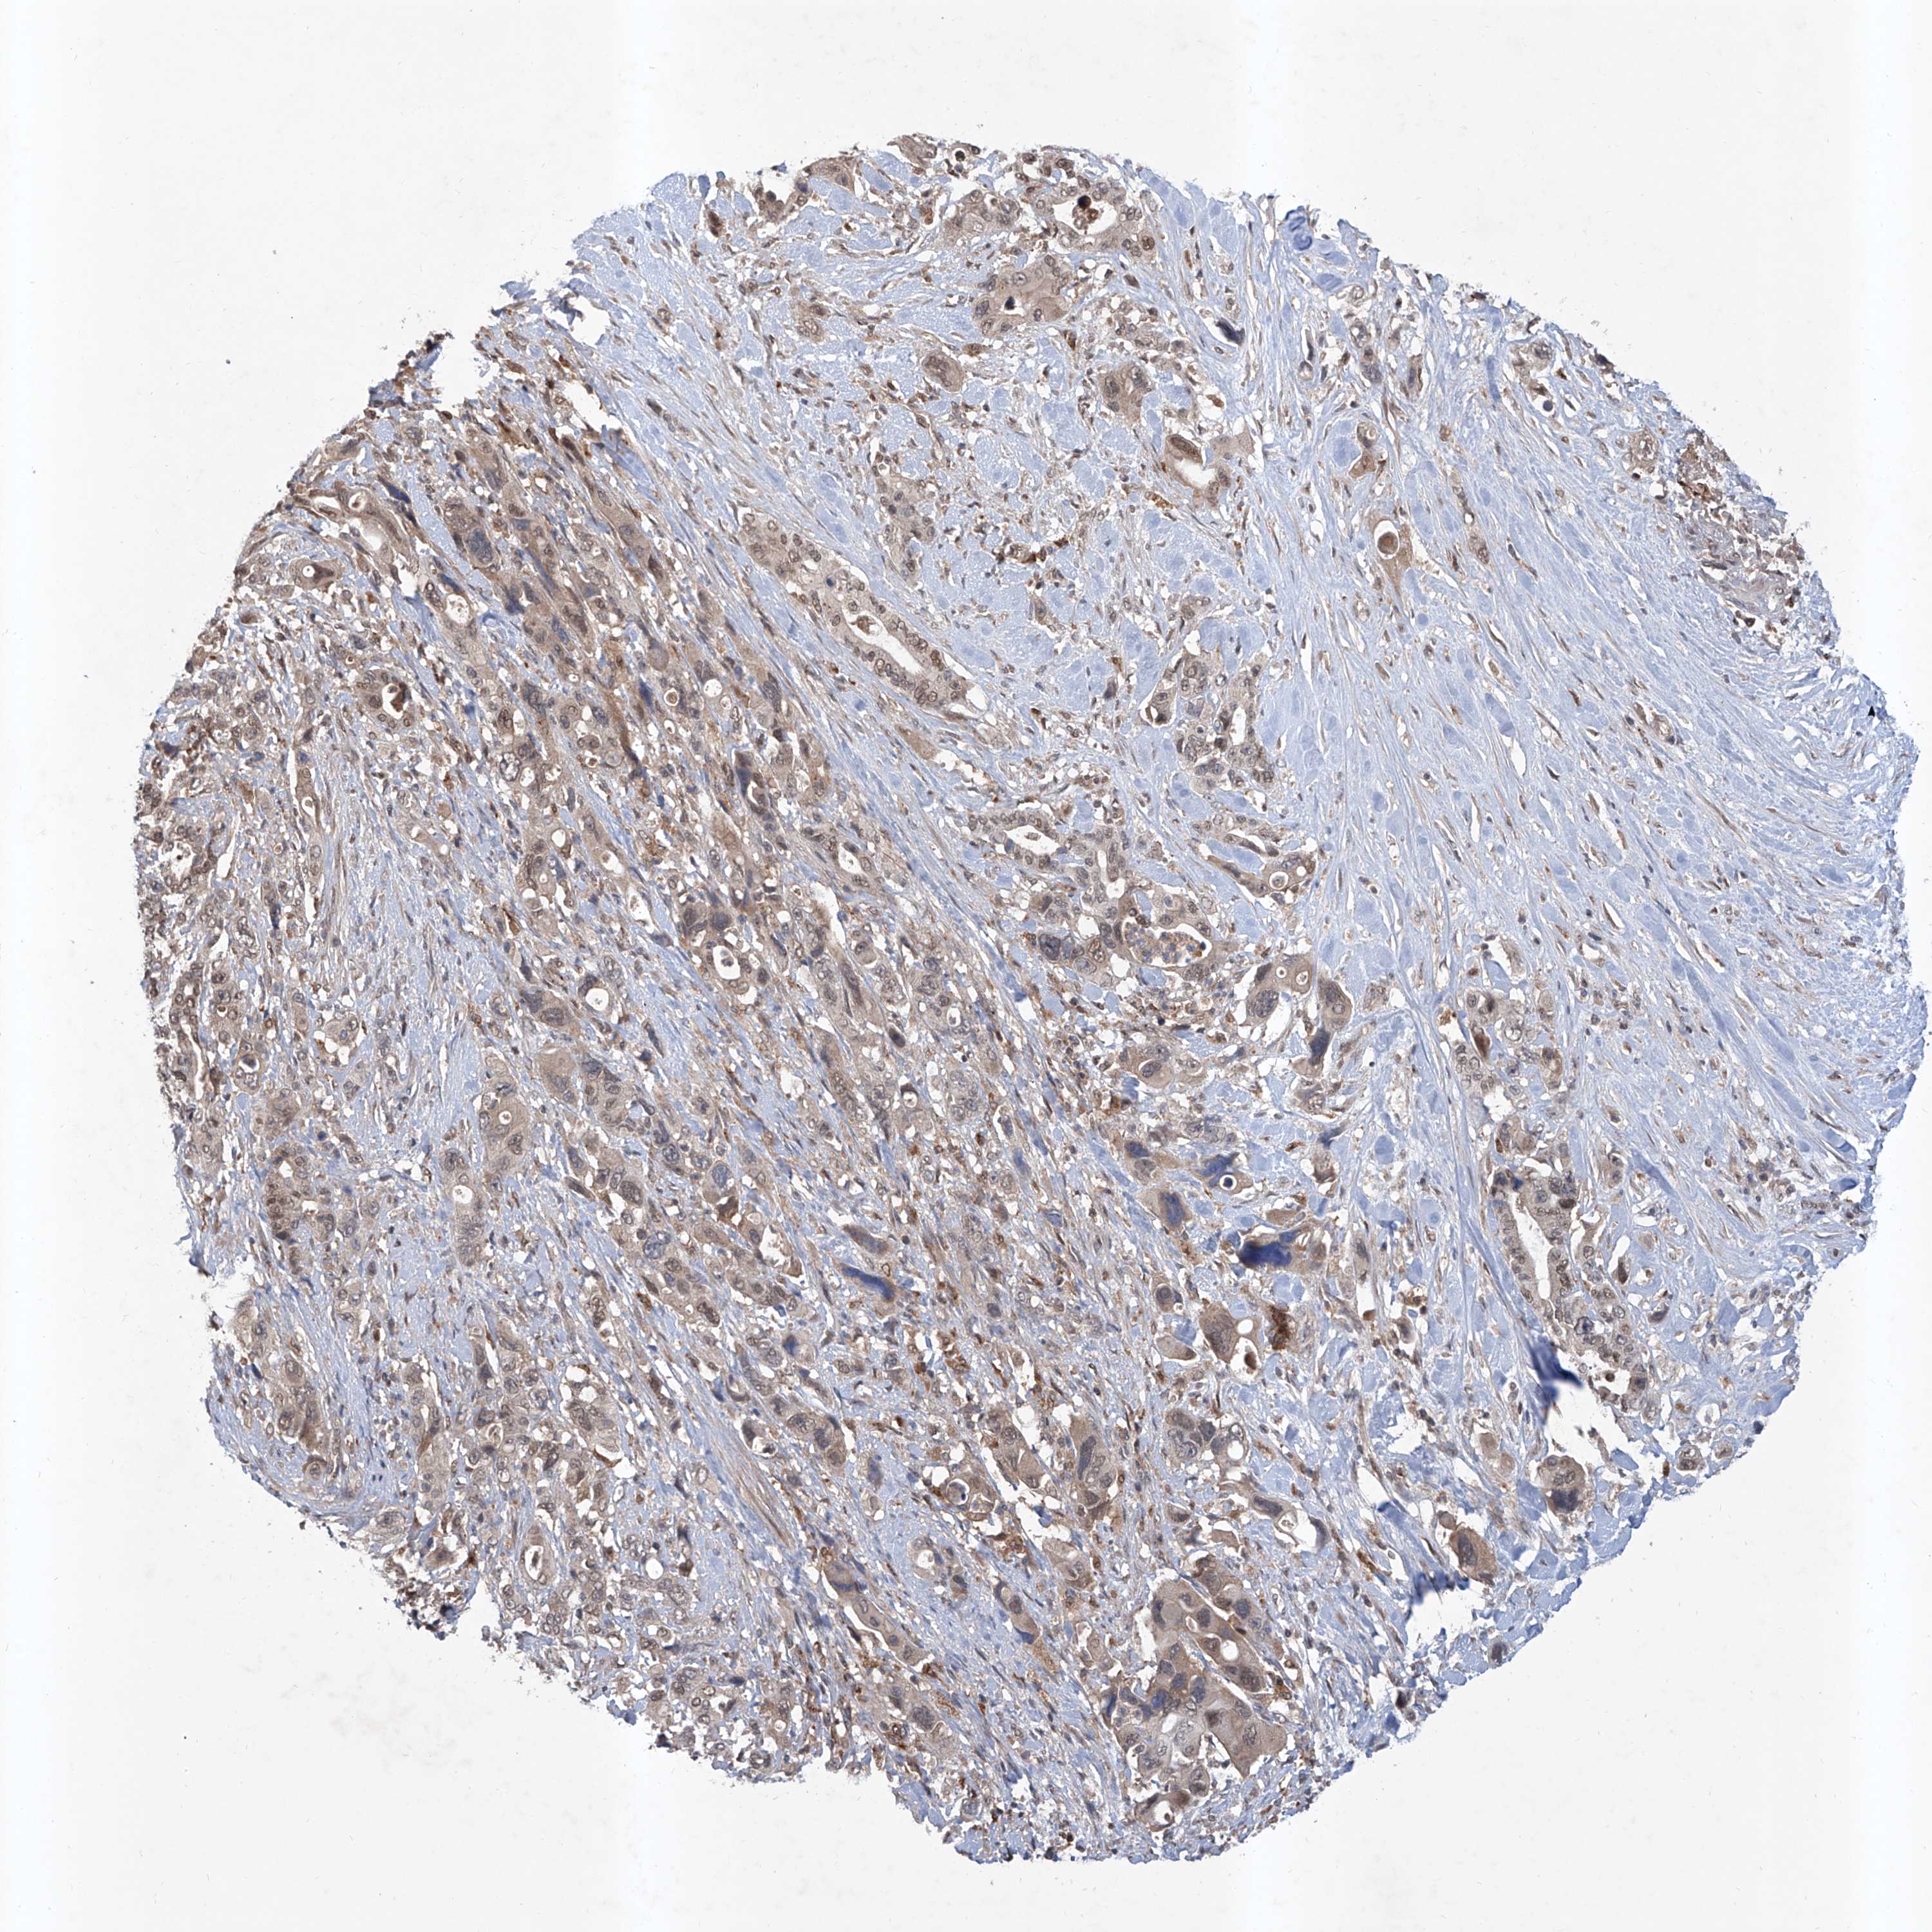

PANCREATIC CANCER - Protein expressioni

A mouse-over function shows sample information and annotation data. Click on an image to view it in a full screen mode. Samples can be filtered based on level of antibody staining by selecting one or several of the following categories: high, medium, low and not detected. The assay and annotation is described here.

Note that samples used for immunohistochemistry by the Human Protein Atlas do not correspond to samples in the TCGA dataset.

Antibody stainingi

Antibody staining in the annotated cell types in the current human tissue is reported as not detected, low, medium, or high, based on conventional immunohistochemistry profiling in selected tissues. This score is based on the combination of the staining intensity and fraction of stained cells.

Each image is clickable and will lead to virtual microscopy that enables deeper exploration of all samples and also displays staining intensity scores, fraction scores and subcellular localization as well as patient and tissue information for each sample.

Antibody HPA028911

Antibody CAB037020

Staining

High

Medium

Low

Not detected

Intensity

Strong

Moderate

Weak

Negative

Quantity

>75%

75%-25%

<25%

None

Location

Nuclear

Cytoplasmic/membranous

Cytoplasmic/membranous,nuclear

Adenocarcinoma, NOS